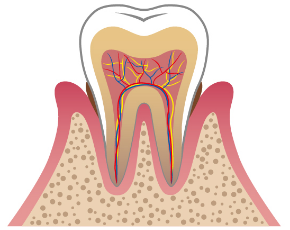

根管治療とは、おおまかにいうと歯の根の中を通る神経の治療のことを指します。

むし歯がかなり進行していると、むし歯菌が歯の神経まで到達してしまうことがあります。

多くのケースでかなりの痛みを伴うことがほとんどなので、こうなってしまった場合は痛んだ神経を取り除き、なおかつ歯の根の中をきれいに洗浄し、薬を詰める必要があります。この治療工程を、根管治療といいます。

この根管治療ですが、非常に難しい治療です。

歯の根の中は直接肉眼で見ることが不可能な上に、歯の神経が通っている管は細く、複雑に枝分かれしているからです。